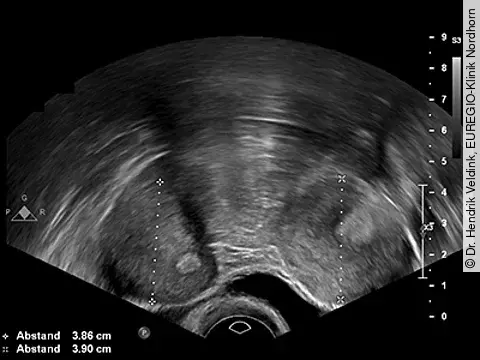

Dr. Hendrik Veldink, EUREGIO-Klinik Nordhorn

QuizAuflösung: Uterusanomalie im transvaginalen Ultraschall

Zu sehen ist ein Uterus bicornis mit einer echoleeren Formation im rechten Uterushorn, bei der es sich um eine Fruchthöhle einer Frühschwangerschaft handeln kann. Im linken Uterushorn ist eine mittelechodichte Formation im Uteruscavum zu sehen, die einem Hämatom entsprechen könnte.